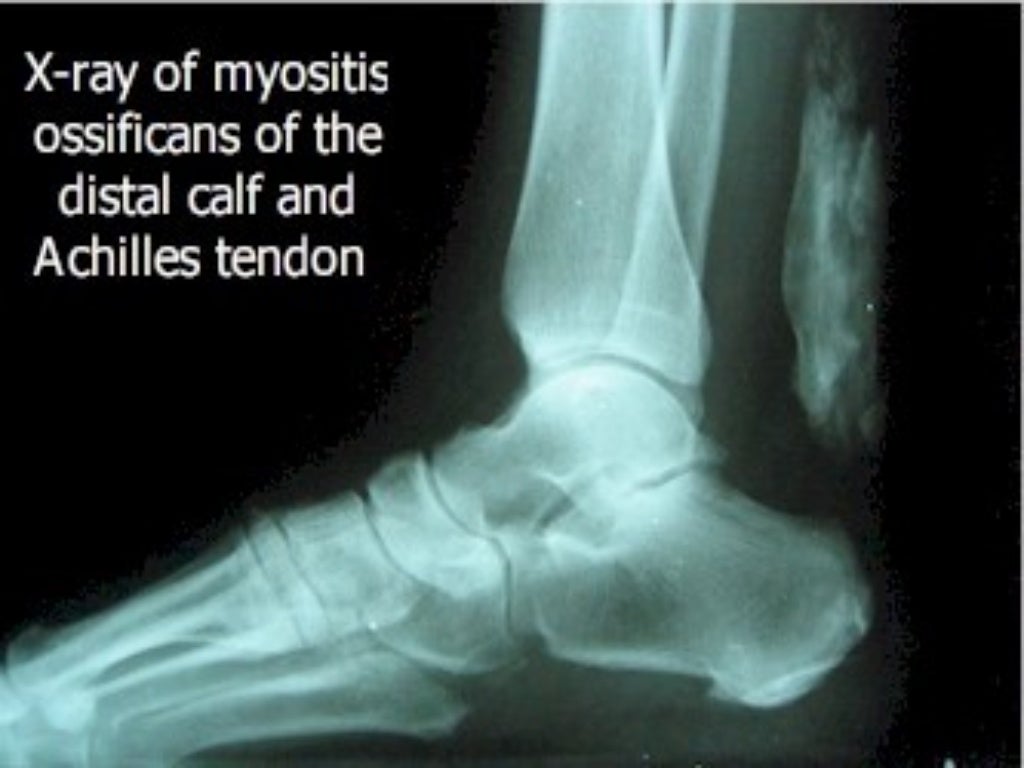

Most (i.e. 80%) ossifications arise in the thigh or arm, and are caused by a premature return to activity after an injury. Other sites include intercostal spaces, erector spinae, pectoralis muscles, glutei, and the chest. On planar x-ray, hazy densities are sometimes noted approximately one month after injury, while the denser opacities eventually seen may not be apparent until two months have passed.

The process of myositis ossificans can be divided into three stages: early, intermediate, and mature. The early phase occurs in the first four weeks of injury with inflammatory phase of bone formation. This is followed by intermediate phase of bone formation (four to eight weeks following injury) where calcification started to occur and is visible on X-rays. During the maturation phase, mature bone started to form. As the maturation continues, the bone will consolidate in the coming months and subsequently bone regression occurs.

Radiologic diagnosis

The radiological features of myositis ossificans are ‘faint soft tissue calcification within 2–6 weeks, (may have well-defined bony margins by 8 weeks) separated from periosteum by lucent zone and on CT, the characteristic feature is peripheral ossification’.

- Radiograph showing myositis ossificans